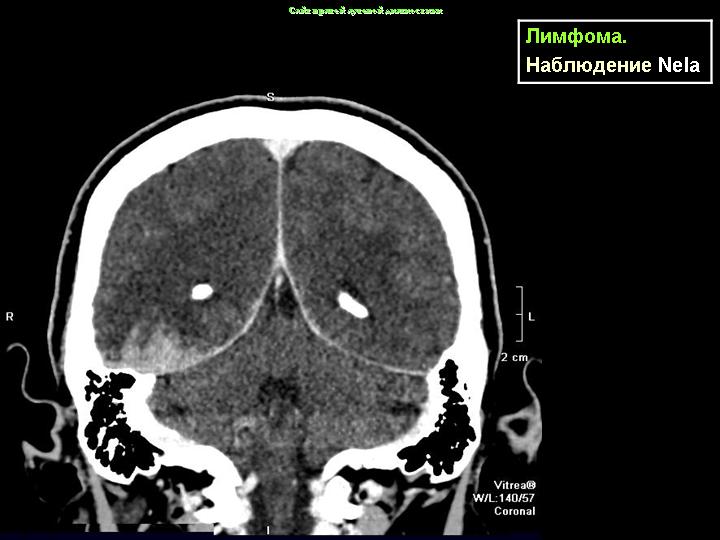

Лимфомы (продолжение набора)

Данные из "интернет-источников".